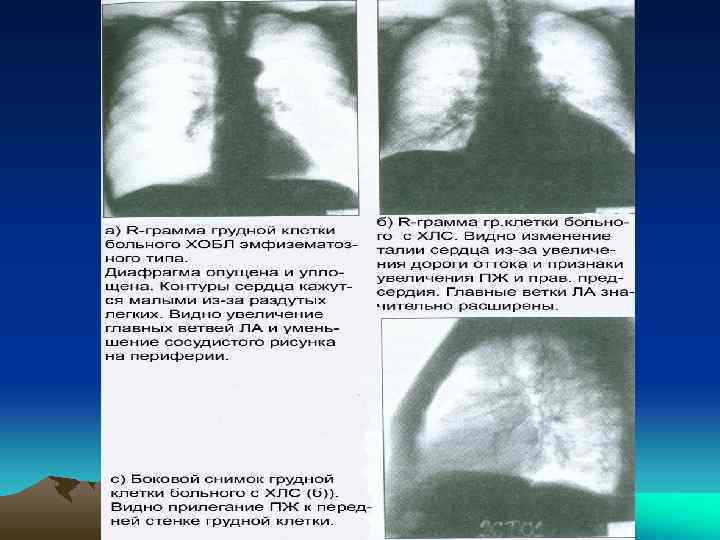

• Эхо. КГ -- ведущий неинвазивный метод оценки функции сердца (патологии клапанов и миокарда), наличия и степени ЛГ, ГПЖ, позволяет визуализировать дилатацию правых отделов сердца (в норме диаметр ПЖ в диастолу <28 мм); верифицировать толщину передней стенки ПЖ (в норме толщина ПЖ составляет 2 -3 мм; диагноз ГПЖ ставится при толщине >3, 5 мм); нарушения профиля движения ПЖ, межжелудочковой перегородки и потоков в области клапанов ЛА и трехстворчатого клапана. Если на них есть регургитация (выявляется у ~50% больных ХОБЛ), то можно рассчитать и ДЛА; • рентгенологическое обследование легких иногда (при выраженной ХСН по ПЖ типу) помогает оценить паренхиму и значительное расширение прикорневых сосудов на фоне обеднения периферического легочного рисунка; выявить гипертрофию ППр и ПЖ на выраженных стадиях болезни; выбухание конуса и ствола ЛА; исключить или верифицировать умеренной тяжести болезни легких или существенное сужение сосудов в системе легочной циркуляции (ясные контры легочных полей на периферии на фоне скудного легочного рисунка и одновременного расширения крупных ветвей ЛА) или ЛГ, возникающую вследствие патологии левых отделов сердца (застой в легочном кровообращении, усиление рисунка легочных вен в верхних легочных полях). При большей части болезней, вызывающих ХЛС, у больных имеются патологические изменения на рентгенограмме легких (выраженная ЭЛ, кифосколиоз, фиброз легких) и выявить проявления ЛГ (дилатацию ствола ЛА и ее ветвей) и ГПЖ в этих условиях трудно.